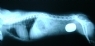

Radio Diagnóstico

La radiología es un método de diagnóstico ampliamente utilizado que nos permite evaluar gran cantidad de patologías, desde fracturas simples hasta problemas de funcionalidad gástrica, renal, etc, utilizando medios de contraste específicos diseñados para tal fin.